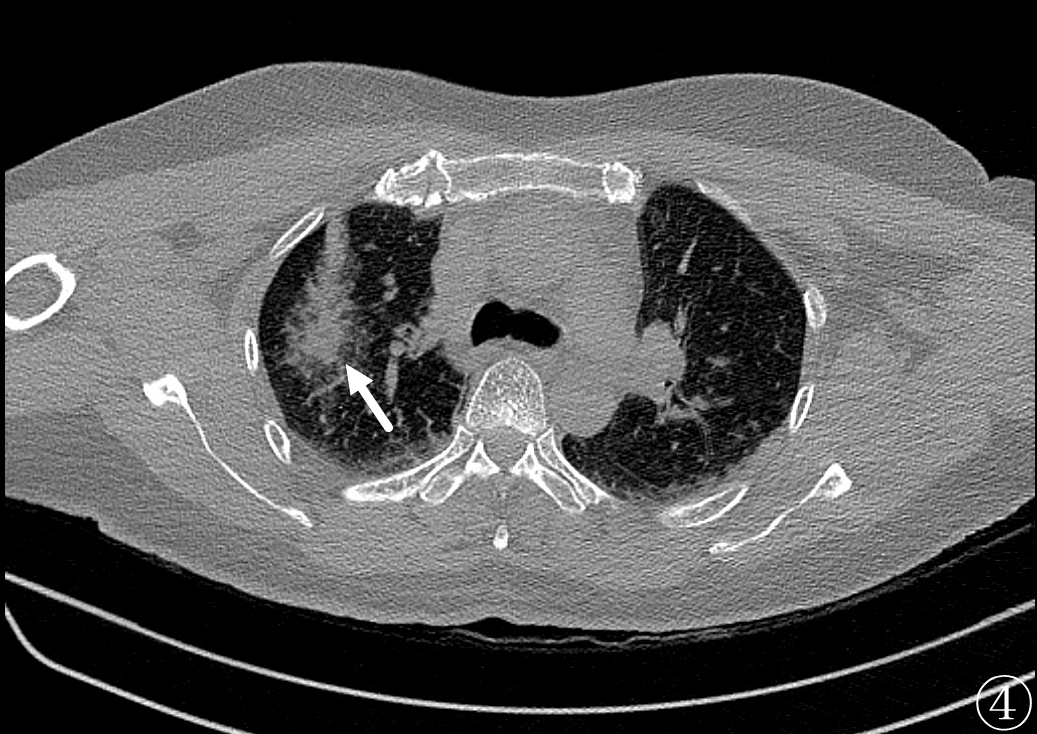

近日,51岁女性体检时发现肺部多发结节,最大一枚直径1.1cm,位于右肺上叶尖段并伴随着恶性影像征象(图①)。

术前进行常规CT扫描确定消融区域及穿刺路径,局部麻醉后利用微波消融针,从体表定位点沿着穿刺路径逐层穿刺到达预定消融区域(图②),予以单次多点消融靶区,最后可见消融后靶区完全覆盖病变区域(图③、④)。手术过程仅耗时约1h,术中肺尖可见少量出血,未发现气胸及咯血等并发症,术后3天复查影像可见消融区完全覆盖病灶(图⑤),病人安然出院,从而达到治愈性消融的目的。